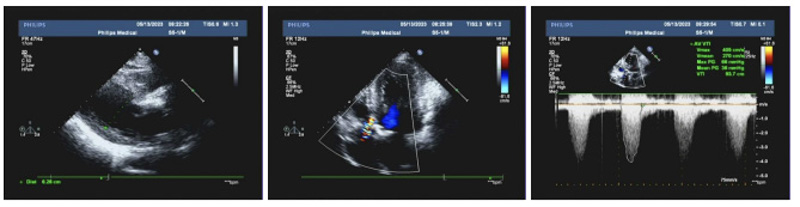

69歲的黃先生因胸悶于日前在心血管內(nèi)科住院檢查,經(jīng)檢查發(fā)現(xiàn)患者主動(dòng)脈瓣重度狹窄并少量反流,瓣口面積僅有0.86cm2。心血管內(nèi)科團(tuán)隊(duì)通過對(duì)患者綜合評(píng)估,根據(jù)其年齡和身體狀況,認(rèn)為實(shí)施微創(chuàng)TAVR手術(shù)是最佳選擇。

患者主動(dòng)脈瓣口面積小,鈣化嚴(yán)重,為手術(shù)帶來了很大困難,術(shù)者小心翼翼地將導(dǎo)絲送入患處,跨瓣、瓣膜定位、釋放球囊……凌晨4:20,隨著大鞘的退出,標(biāo)志著一場與死神賽跑以勝利謝幕。在多學(xué)科緊密協(xié)作下,急診TAVR手術(shù)圓滿成功,患者術(shù)后血流動(dòng)力學(xué)指標(biāo)即刻得到改善,跨瓣壓差從160mmHg下降到僅為5mmHg!復(fù)查心臟彩超提示主動(dòng)脈瓣狹窄完全解除!患者各項(xiàng)生命征數(shù)值平穩(wěn),病情轉(zhuǎn)危為安!